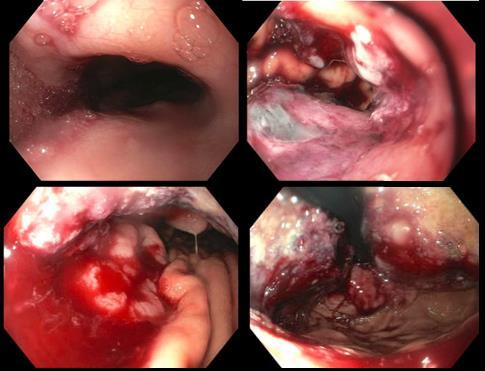

LARYNGEAL SYNOVIAL SARCOMA THAT METASTASIZED TO THE HEART

Christopher N. Matthews1 , Syed Farrukh Mustafa1 , Sidra Salman1 , Akshaya

Gopalakrishnan1, James Salonia1 , Deepika Misra1

1Mount Sinai Morningside-West Hospitals, Icahn School of Medicine at Mount Sinai, New York, NY, United States

Presented at the American College of Cardiology (ACC) Annual Meeting that was held in New Orleans, Louisiana, United States from March 4-6, 2023.